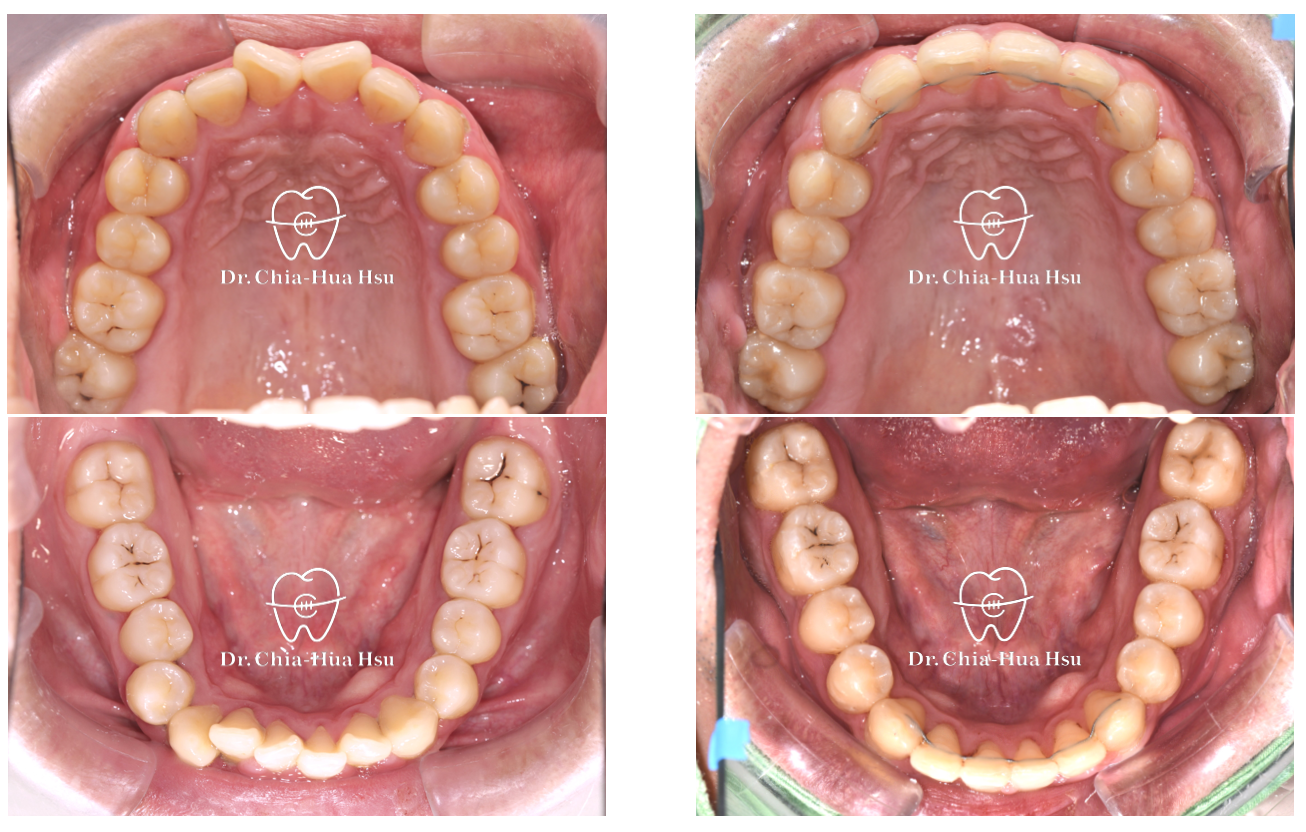

治療前

治療後